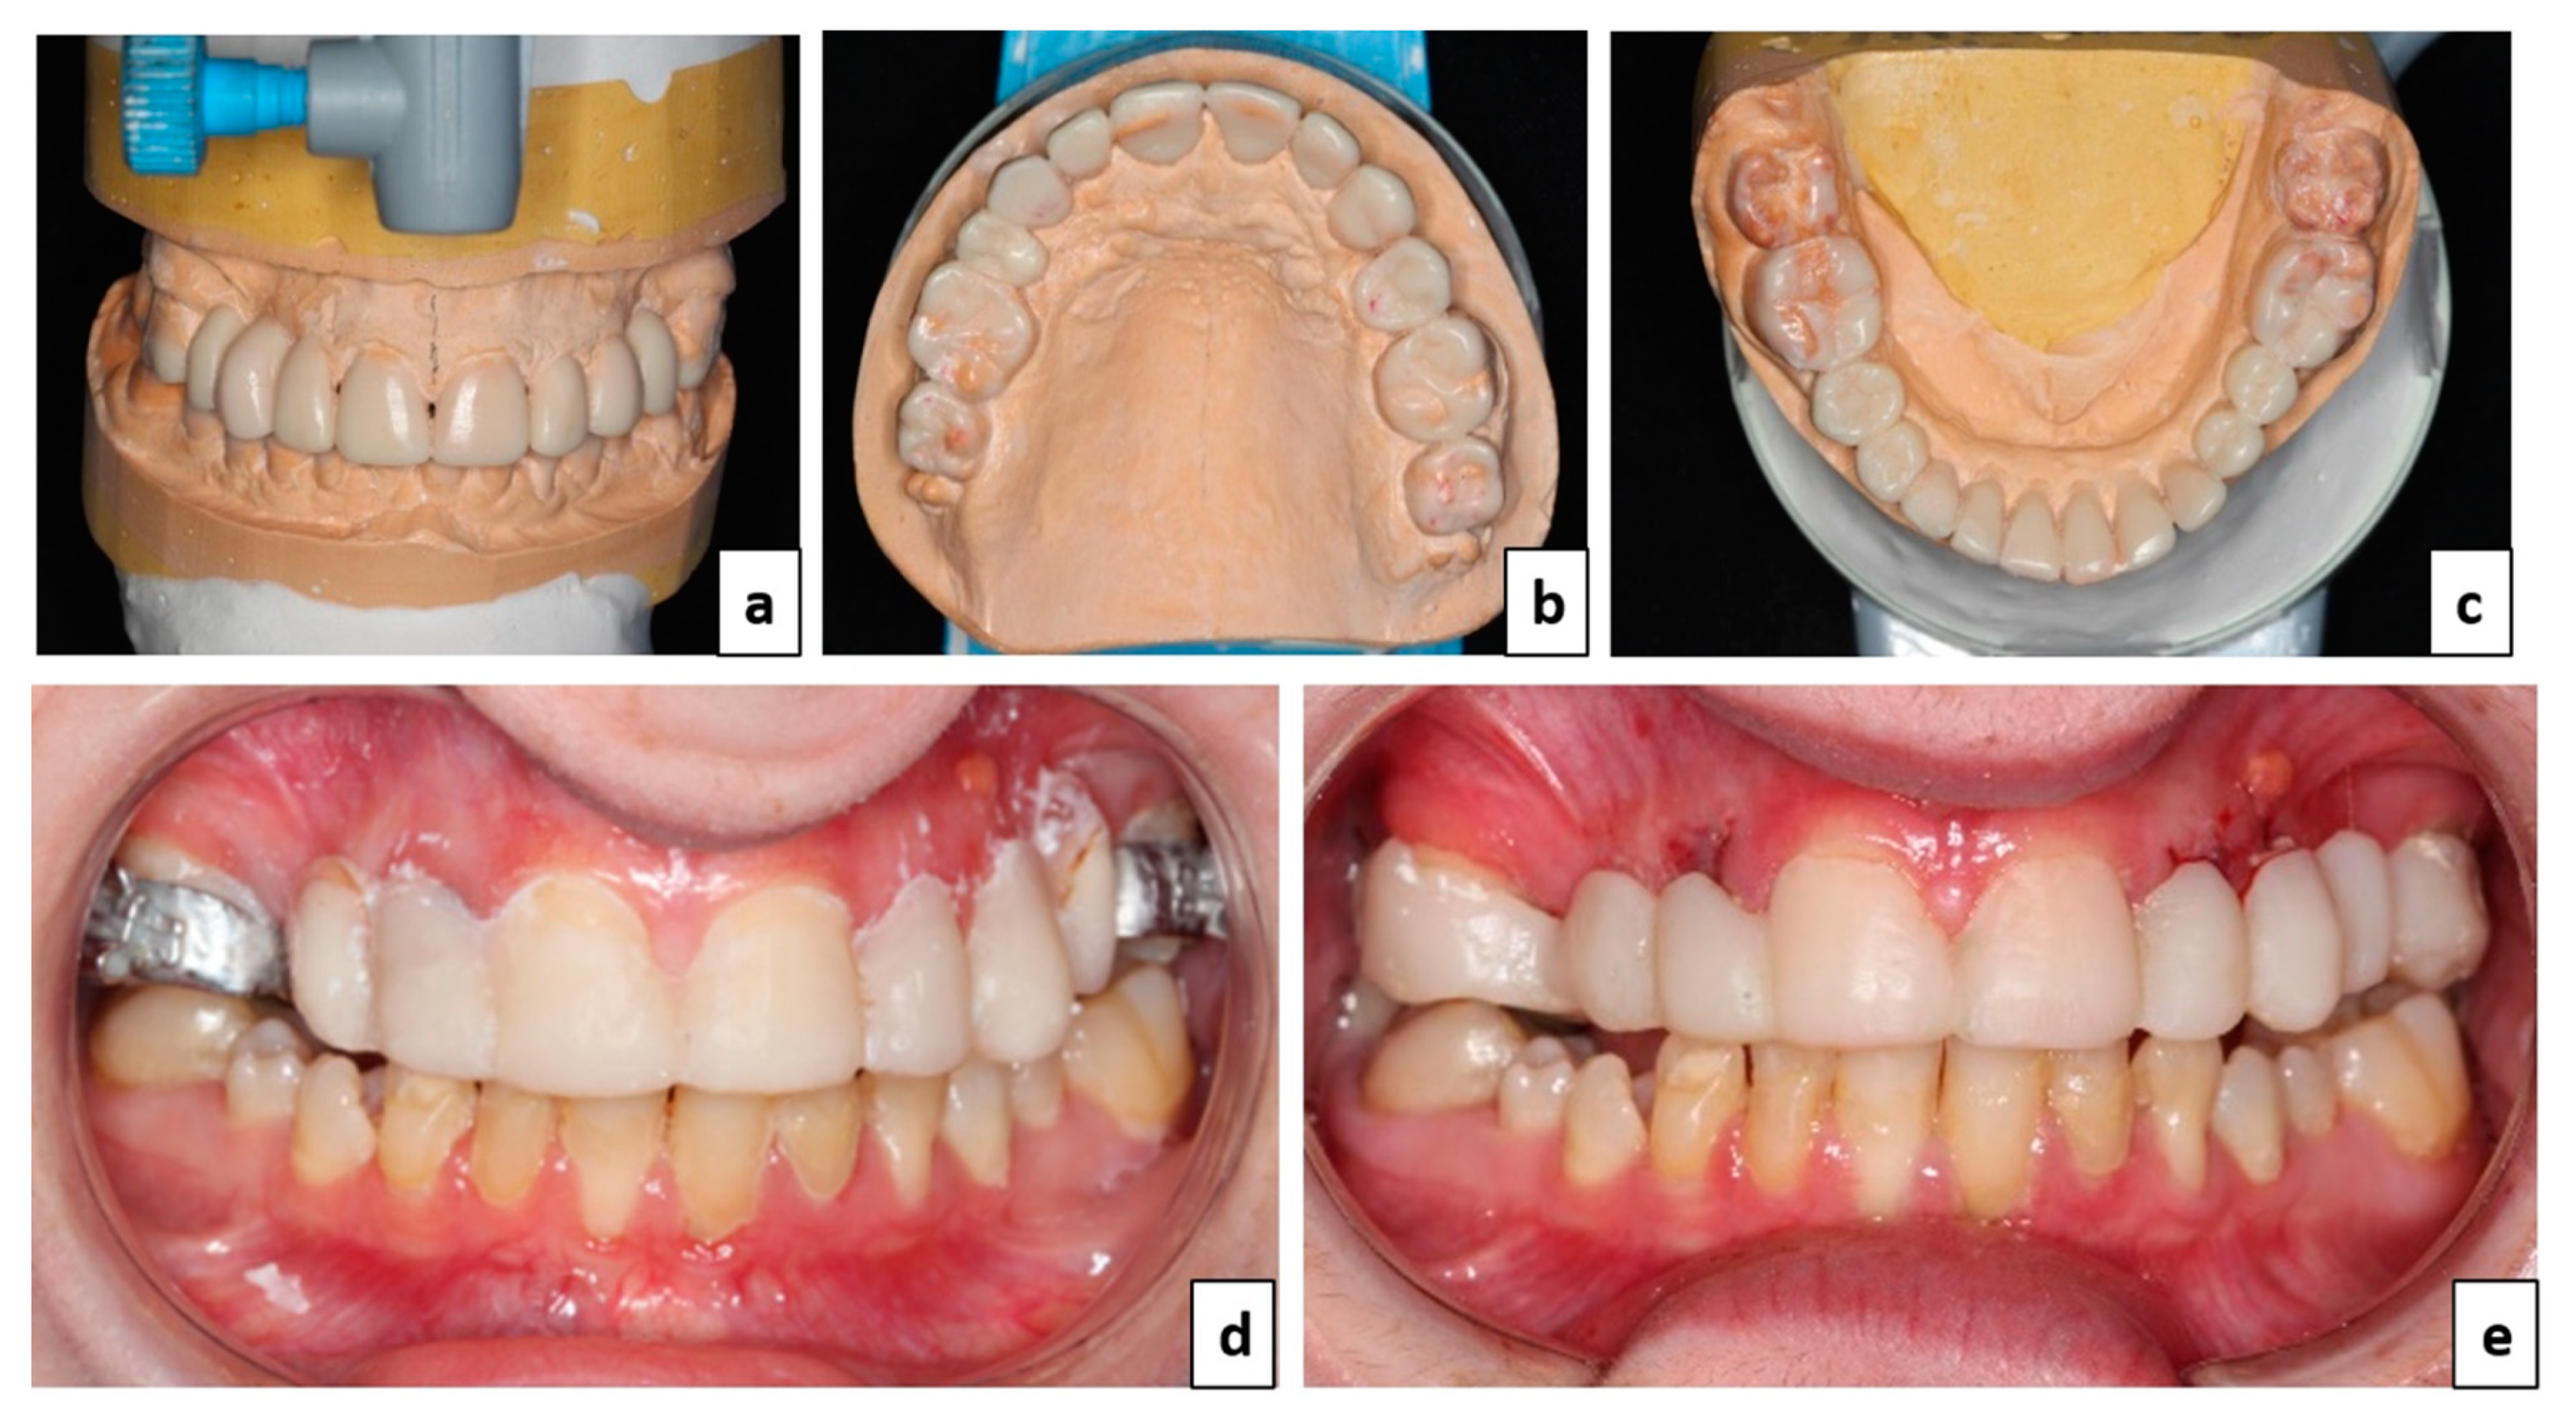

3. Treatment Plan

4. Therapeutic Management